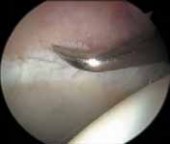

1. Most symptomatic labral tears are managed with selective débridement of the damaged portion ( TECH FIG 1).

2.

Emphasis is given to preserving healthy tissue, because removal of normal labrum can lead to poorer results.

3.

A complete joint survey is performed with thorough inspection and palpation of the labrum, identifying its damaged portion.

4.

Most labral resection is carried out with a power shaver, debulking the damaged tissue.

1.

Hand instruments and an arthroscopic knife may aid in this resection.

It is important to preserve the healthy tissue but create a stable transition zone when completing the débridement.

A radiofrequency device is especially useful for this because of the limited maneuverability imposed by the architecture of the joint.

Diseased tissue has an increased water content and responds selectively to the thermal device.

TECHNIQUES A B TECH FIG 1 • Arthroscopic view of a right hip from the anterior portal. A. A fragmented labral tear with degeneration within its substance is identified. B. Débridement is initiated with the power shaver. C. A portion of the comminuted labral tear is conservatively stabilized with a radiofrequency probe. D. The damaged portion has been removed, preserving the healthy substance of the C D labrum. LABRAL REPAIR